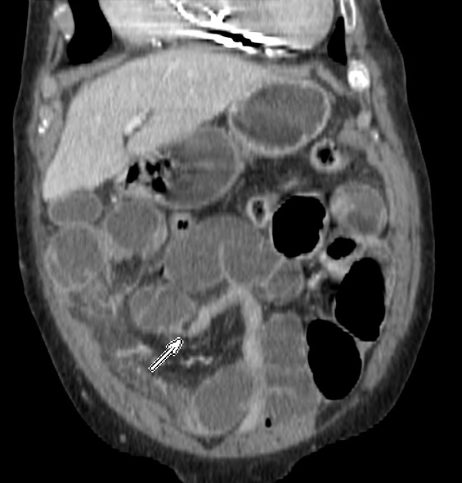

INVAGINACIÓN INTESTINAL.

La invaginación intestinal es la introducción telescópica de un segmento de intestino junto con su mesenterio, dentro de la luz de otro segmento contigüo más distal. En una invaginación, la porción de intestino que se invagina, arrastra su meso acompañante, lo cual origina una compresión del retorno venoso. Si esto no se soluciona a tiempo, se produce edema, hemorragia, obstrucción y gangrena.

En el adulto es poco frecuente, constituye solo el 5% de las invaginaciones. Entre los 30 y 50 anos de edad. Más frecuente en hombres que en mujeres (2:1) con clínica subaguda crónica siendo un diagnóstico difícil debido a la poca prevalencia y a la variabilidad de los hallazgos clínicos (dolor abdominal, episodios repetidos de suboclusión intestinal, sangrado rectal…).

El diagnóstico actual de la se realiza mediante TC abdominal:

- El hallazgo patognomónico es el signo de la escarapela o diana identificable en la TC o ecografía.

- Podemos ver la imagen de “Intestino dentro de intestino” gracias a las reconstrucciones multiplanares.

Invaginación de Intestino Delgado

- Son más frecuentes que las de colon

- Es más frecuente la invaginación esporádica. Si hay lesión subyacente, suele ser benigna.

- Las causas malignas son menos frecuentes (15-30%), en general metástasis, sobre todo de melanoma.

- El linfoma constituye el 20-40% de todos los tumores malignos de ID.